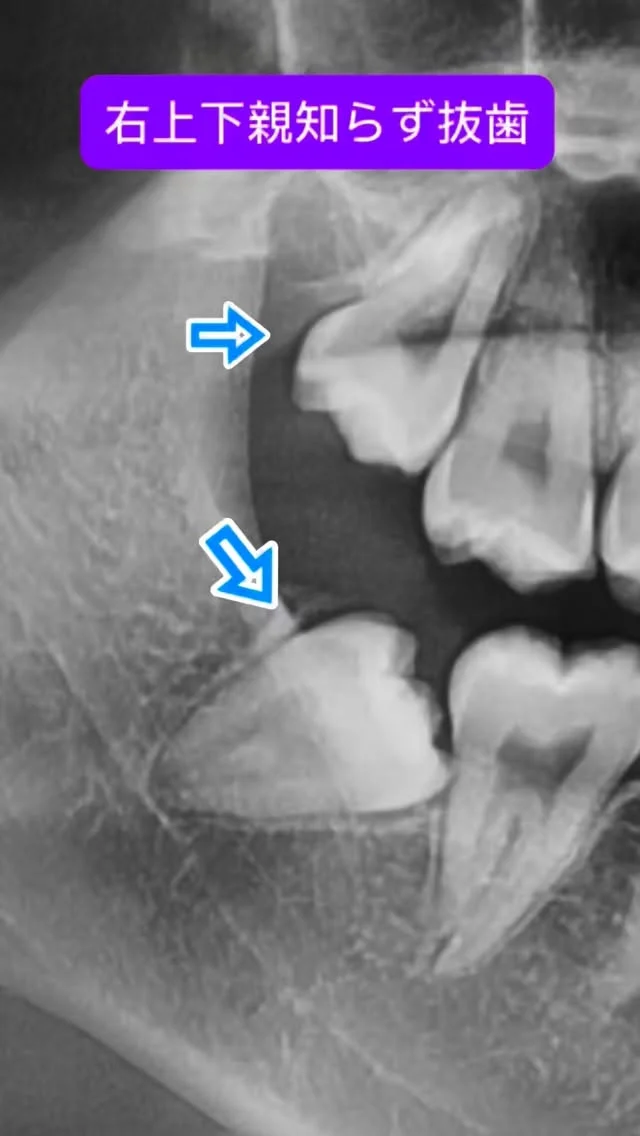

大学病院や総合病院で長年、親知らず抜歯や歯根端切除術などの小手術から、全身麻酔下で行う顎矯正手術(骨切り)、口腔腫瘍、インプラント治療など幅広い口腔外科診療・手術に携わってきました。

これまでに数多くの難症例を担当し、「安全、スピーディーかつ合併症を低減する手術」を常に意識してきました。特に骨切り手術では、機能面の改善だけでなく、顔貌のバランスや審美性にも配慮し、口元の自然な美しさを追求しています。

親知らずや顎の形のお悩み、外科的な処置に不安をお持ちのかたも、ぜひ一度ご相談ください。専門医として、丁寧に寄り添いながら適切な治療をご提案いたします。